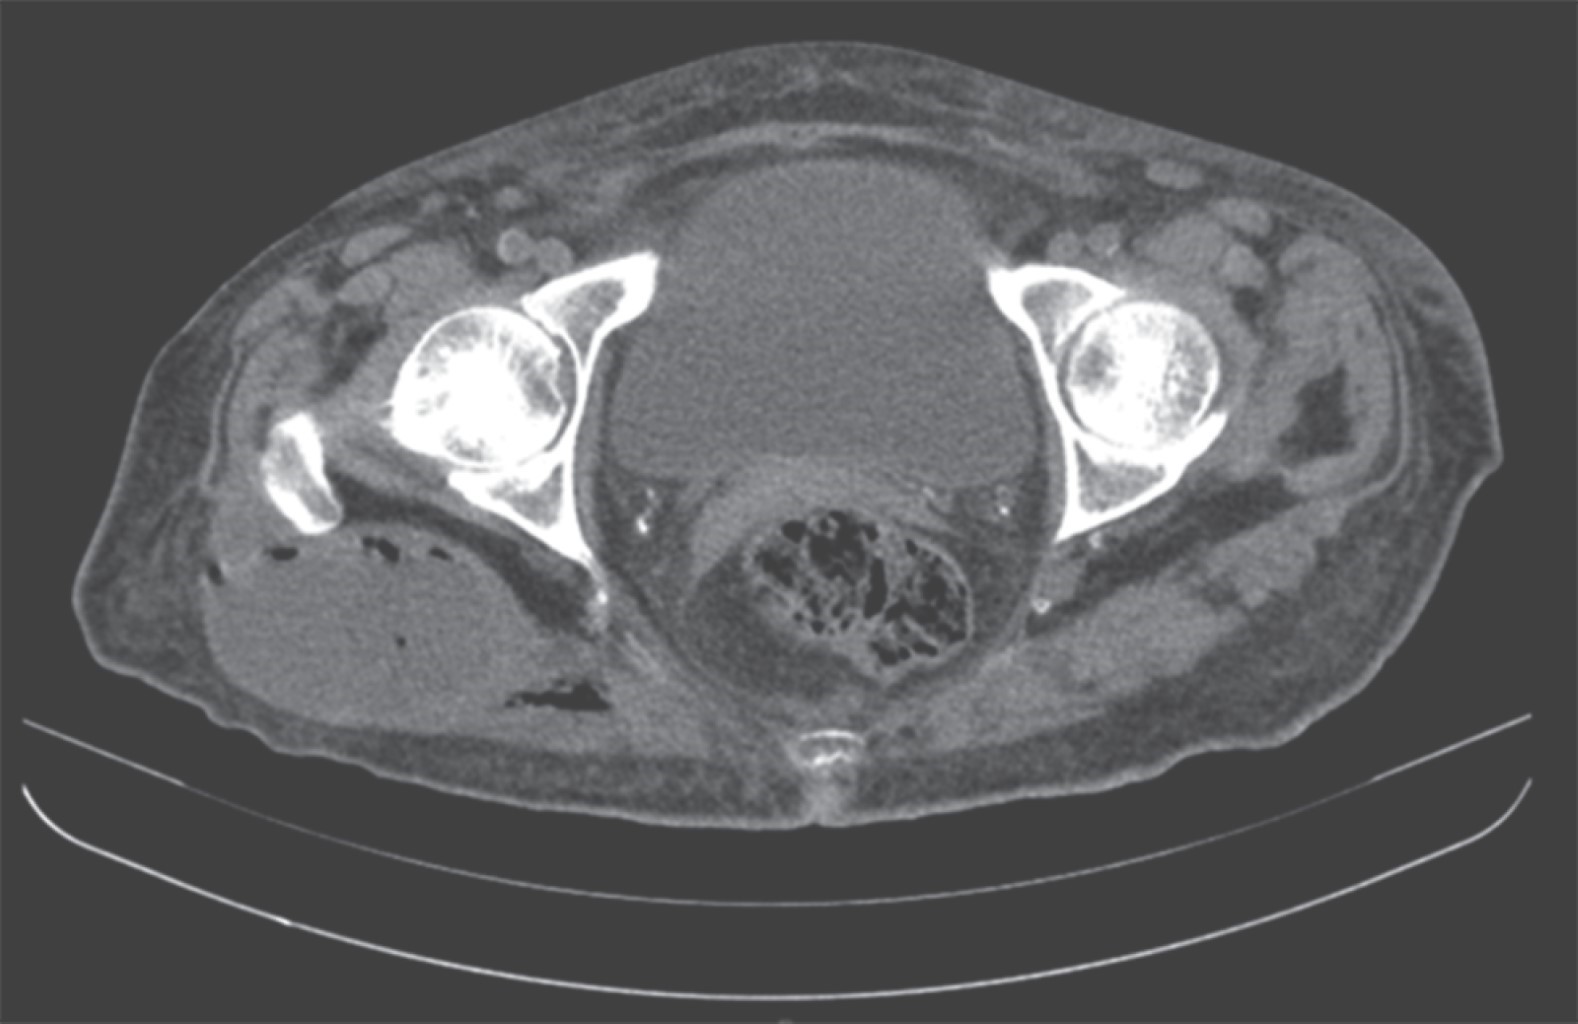

Necrotizing fasciitis due to Klebsiella pneumoniae secondary to intramuscular gluteal injection managed with a negative pressure system

Necrotizing fasciitis is a serious, rare and fast progressing infection, which that is difficult to diagnose in the early stages. It produces thrombosis of the microcirculation with involvement of the subcutaneous cellular tissue and muscle fascia and is related to high mortality. Documented cases of necrotizing fasciitis in which Klebsiella pneumoniae is the etiologic agent are extremely rare and have a mortality rate of 70%. We present the case of a 57-year-old woman who developed necrotizing fasciitis after an intramuscular injection in the right gluteus. She was handled with negative pressure therapy at the General Hospital of Zacatecas "Luz González Cosío" showing a good progress, with satisfactory functional and aesthetic results. The negative pressure therapy facilitated the treatment and evolution of the patient considerably, favoring the granulation of the wound and the definitive closure. We underline highlight the usefulness of negative pressure therapy in the management and healing of wounds, staving off avoiding complex reconstructive surgeries.

Figure 1